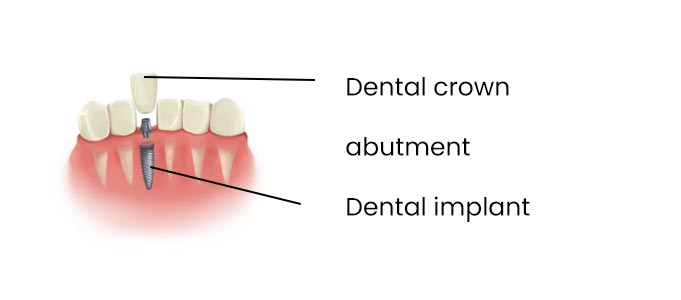

How Dental Implant Surgery Can Affect Pain and Recovery Outcomes Dental implants are the first choice to restore single or…

How Dental Implant Surgery Can Affect Pain and Recovery Outcomes Dental implants are the first choice to restore single or…

Addressing Common Concerns about Dental Implants: Pain, Recovery, and Long-Term Success Dental implants stand at the forefront of modern dentistry…

How do I choose the Best Dental Clinic in Ahmedabad for My Dental Implants? Implants are an advanced and effective…

I feel my implant is moving. What could be the reason? The replacement of missing teeth through dental implantation has…